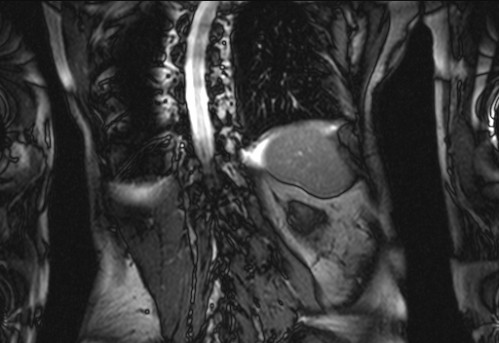

Auffälliges Abdomen bei der Vorsorgeuntersuchung einer älteren Dame

ICD: C64

68 Jahre alte Frau. Sie geht zur Darmspiegelung im Rahmen ihrer Krebsvorsorgeuntersuchung. Der Internist bemerkt bei der ergänzenden sonografischen Untersuchung des Abdomens einen auffälligen Befund.